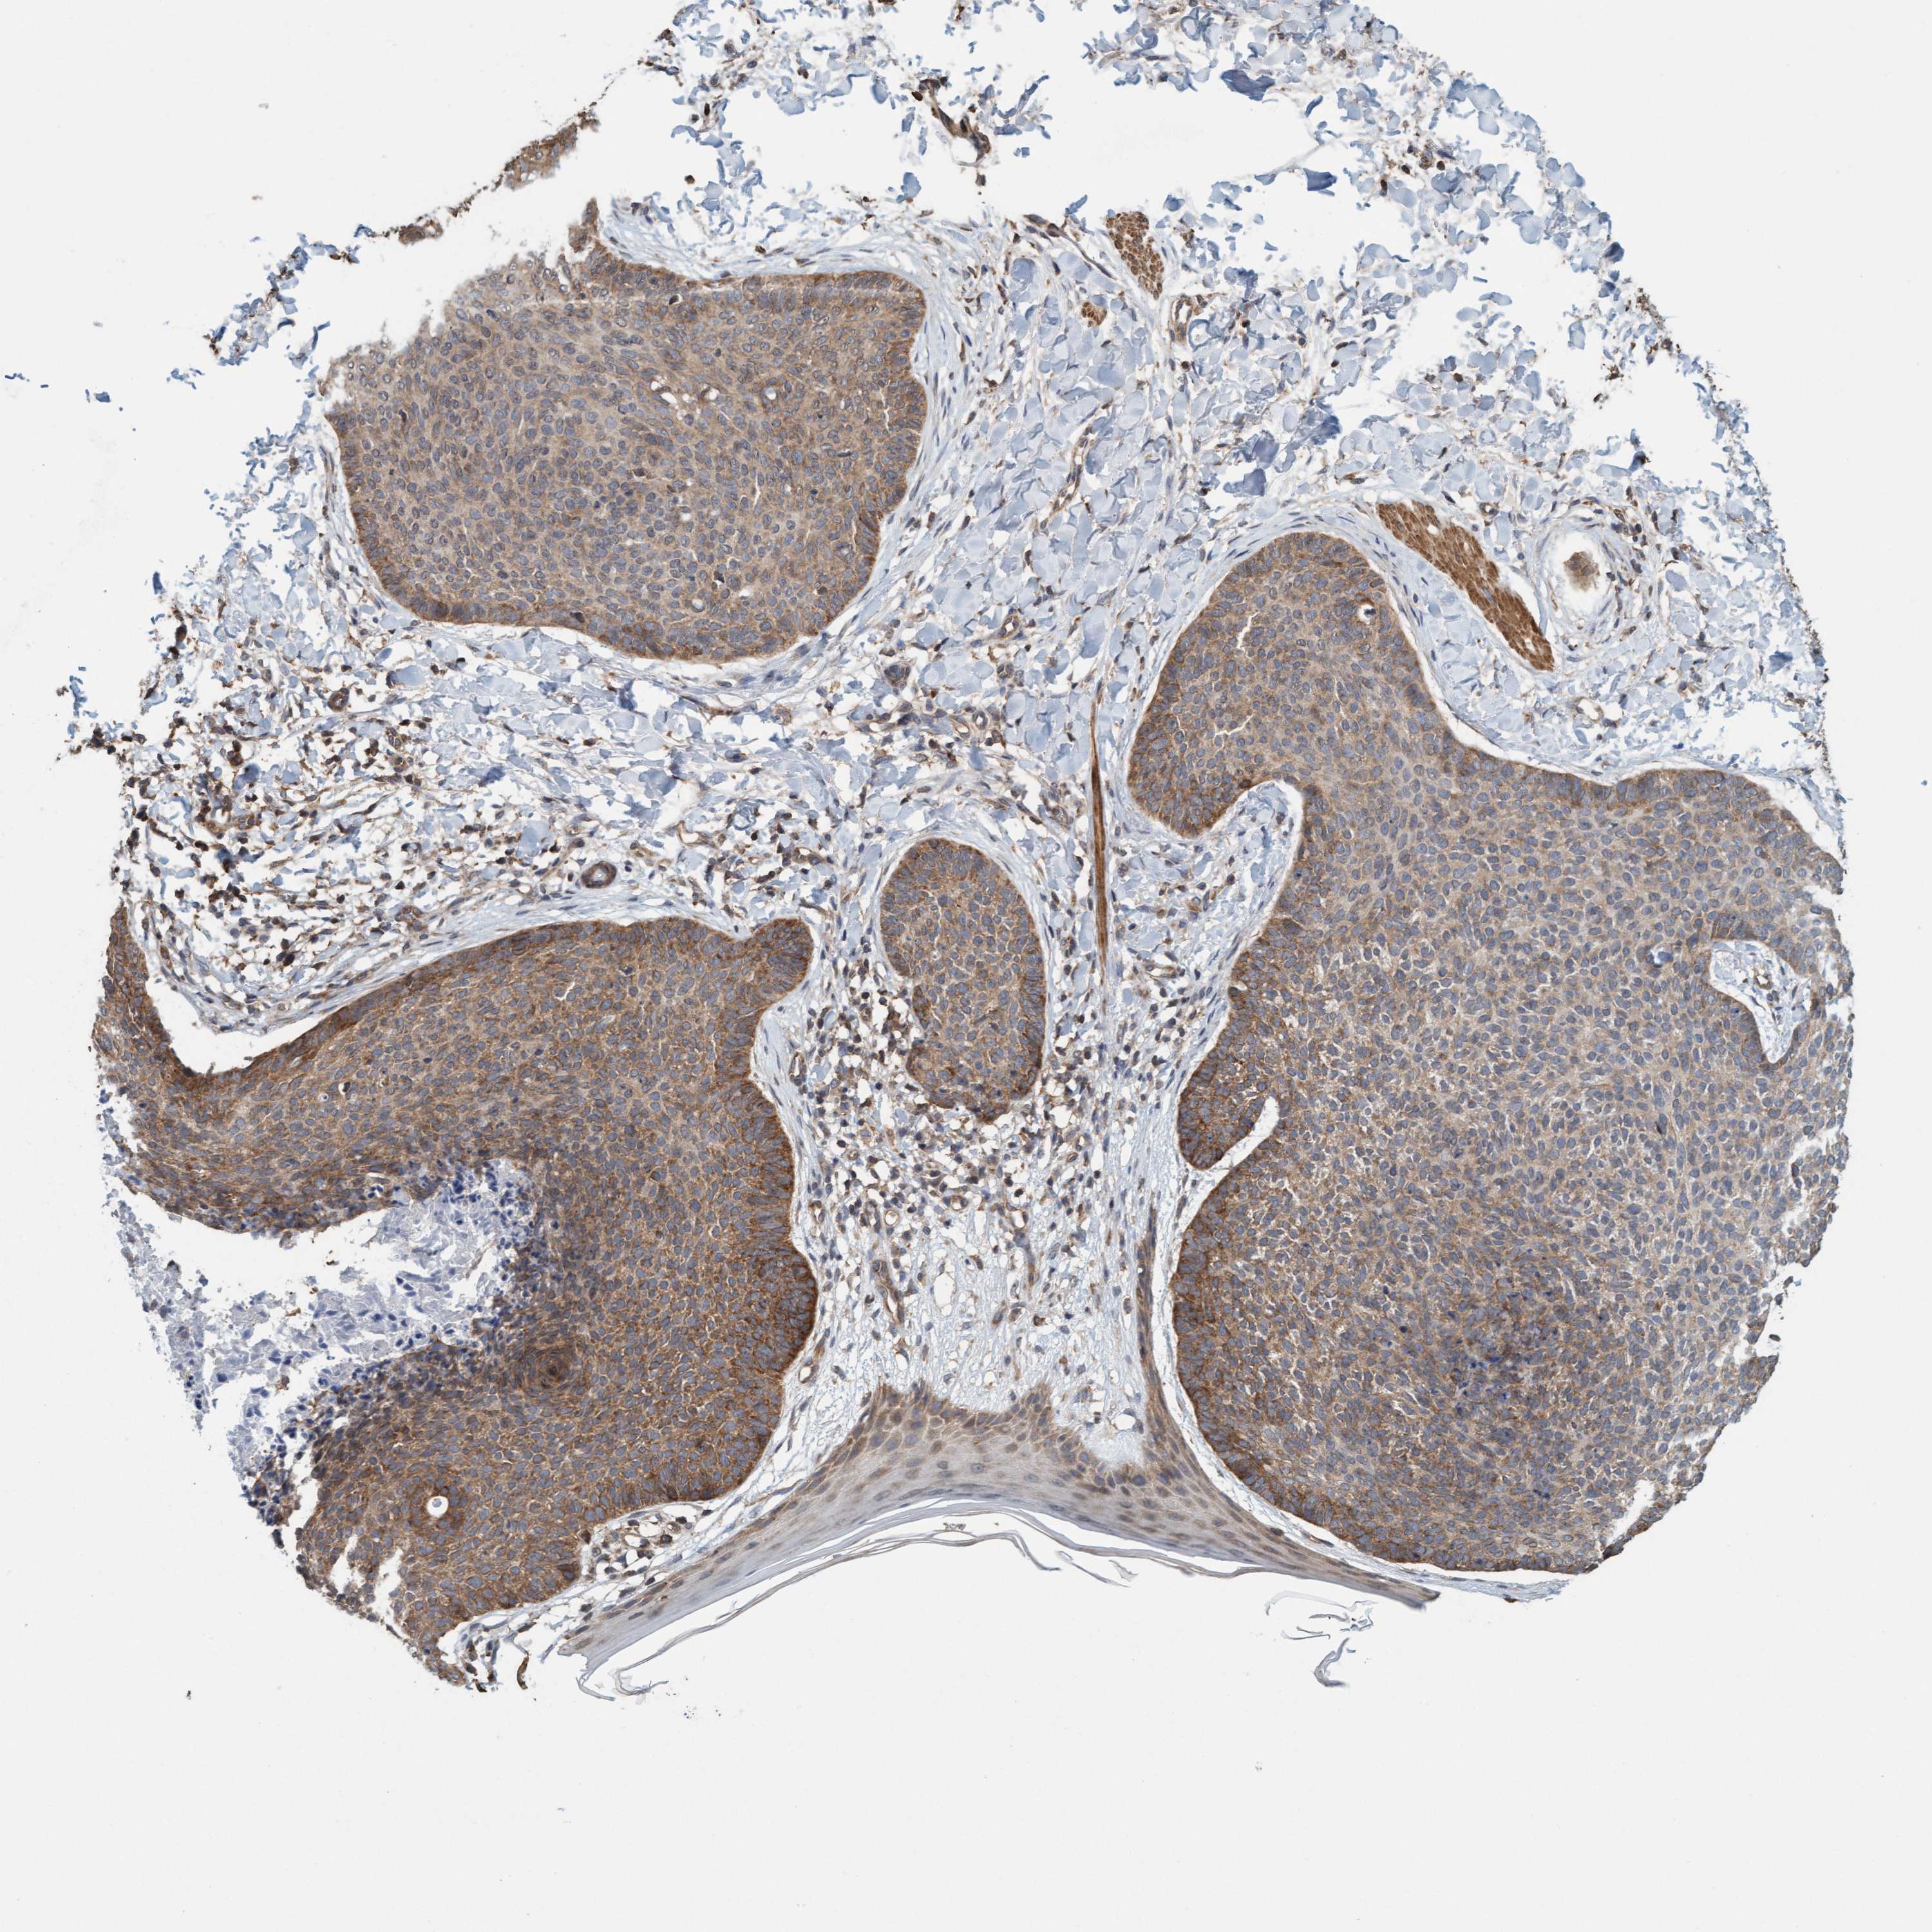

SKIN CANCER - Protein expressioni

A mouse-over function shows sample information and annotation data. Click on an image to view it in a full screen mode. Samples can be filtered based on level of antibody staining by selecting one or several of the following categories: high, medium, low and not detected. The assay and annotation is described here.

Each image is clickable and will lead to virtual microscopy that enables deeper exploration of all samples and also displays staining intensity scores, fraction scores and subcellular localization as well as patient and tissue information for each sample.

Antibody CAB011205

High

Strong

>75%

Location

Squamous cell carcinoma, NOS